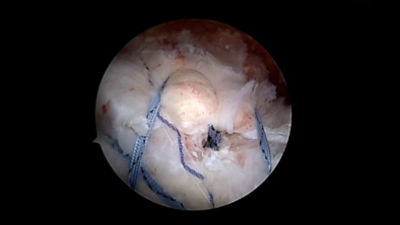

InSpace subacromial balloon spacer

The industry’s only subacromial balloon spacer designed to treat patients with massive irreparable cuff tears, offering the potential for early functional recovery and pain relief.2